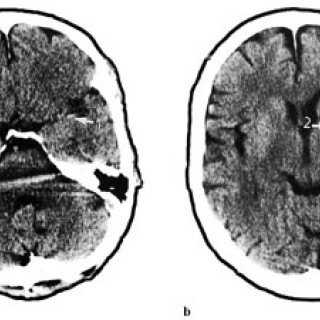

Gassemboli kan oppstå som følge av kirurgi, diagnostiske prosedyrer, traumer, lungeskader, bruk av hjerte-lunge-maskin og ved trykkfallssyke (1, 2). Gassemboli er en sjelden komplikasjon, men kan resultere i betydelig morbiditet, i verste fall død. Det er grunn til å tro at særlig iatrogen gassemboli i liten grad blir erkjent. Det er viktig at leger og sykepleiere i større grad blir oppmerksom på problemet, da de fleste pasientene vil kunne unngå sekvele med adekvat behandling. Med gassemboli menes vanligvis luftemboli, men med dagens bruk av andre gasser i medisinsk øyemed kan eksempelvis...